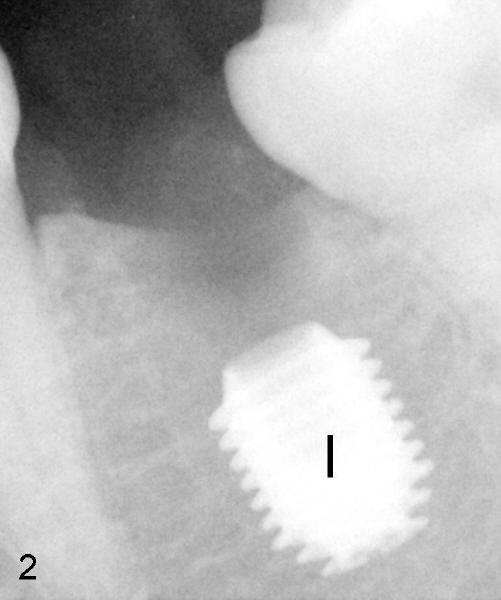

A 6x8 mm Bicon implant (3 mm post) was placed as distal as possible (I in Fig.2). Three months later, the implant was uncovered with evidence of osteointegration (arrowheads in Fig.3). A 4x6.5 mm 0 degree non-shouldered abutment with 3 mm post (A) was inserted into the implant well. The flat surface of the abutment needed to face distal in order to seat the abutment without interference. Return to main article